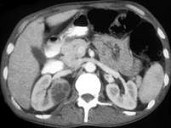

- 多项选择题男,35岁, 右侧腰部疼痛伴发热,根据所示图像, 最可能的诊断是 ( )

A、右侧肾脓肿

B、右侧单纯性肾囊肿

C、右侧囊性肾癌

D、右肾转移癌

E、前列腺脓肿